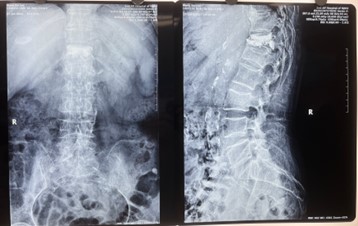

術中切口5毫米,在在C形臂X光機透視指引下,確定進針的方向及進針的深度,經椎弓根向椎體置管,建立通道,插入骨擴張器(球囊)。球囊擴張恢復椎體高度,并在椎體內形成空腔,確定骨水泥的注入劑量,并注入骨水泥觀察其擴散情況,大大降低了手術風險,縮短了手術時間。

C形臂X光機作為手術中的重點設備,能準確定位,手術過程中即時觀看、即時做決策,在C形臂X光機的指導下,醫生能迅速、精準確定患者手術的部位。從而極大縮短手術時間,提高手術效率和質量,減輕患者痛苦,讓手術更加快捷且安全。

對比一些9英寸的平板C形臂,普愛醫療PLX119C大平板C形臂,30CM*30CM想(30CM*30CM)的成像范圍,一次性可成像5節腰椎,有效減少小視野C形臂難以一次性確定傷椎,可能需要進行多次拍攝的問題,使得手術效率更快、更準確。